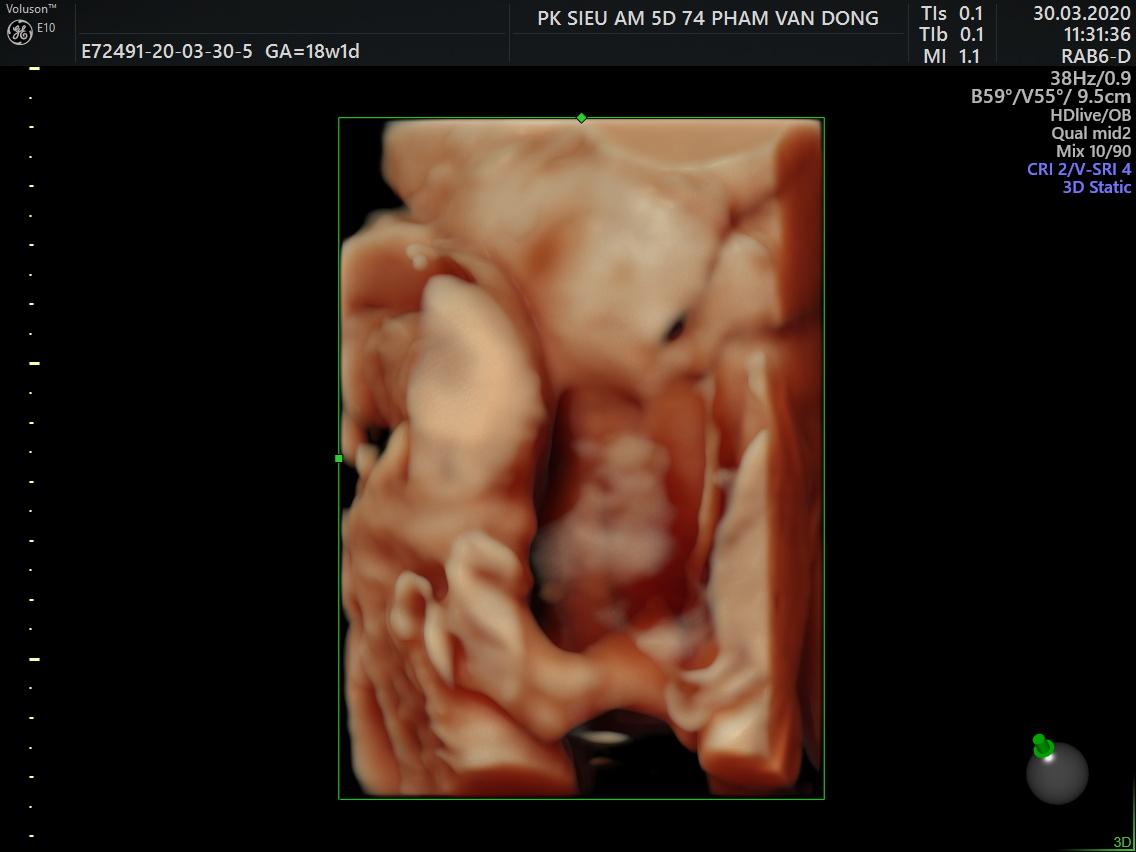

Chim non 18w đây ạ,các mom khoe chim non e ngắm với nè